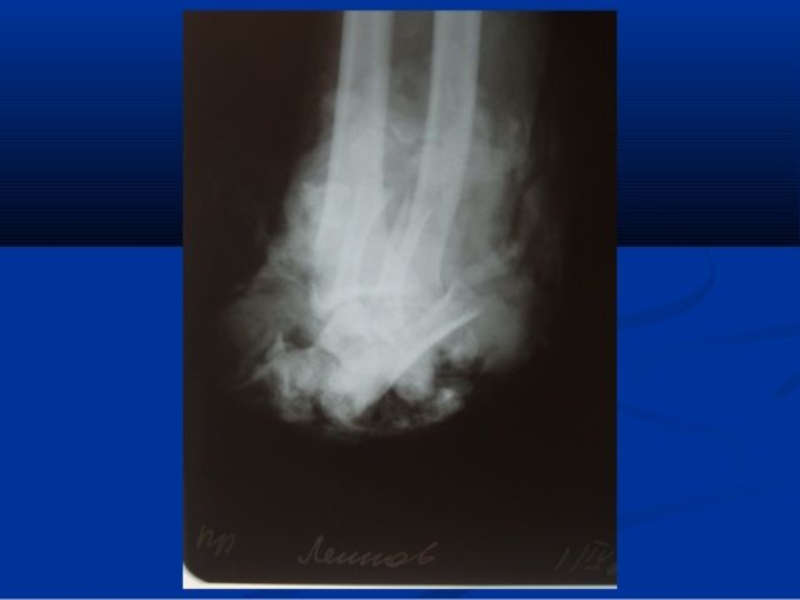

Слайд 67Протезирование нижних конечностей в зависимости от уровня ампутации

В настоящее время

принято выделять несколько уровней ампутации нижних конечностей, в соответствии с

которыми распределяются и варианты протезирования. Таким образом, в распоряжении специалистов имеются протезы переднего отдела стопы, по Лисфранку (Lisfranc), по Сайму (Syme) и Пирогову, протезы голени, бедра, протезы по Гритти (Gritti), протезы после вычленения колена или бедра, после межподвздошно-брюшной ампутации или межподвздошно-брюшной экзартикуляции.